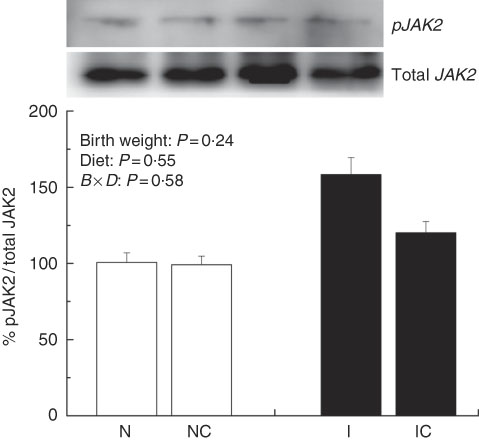

The IUGR rats exhibited higher (P<0·05) phosphorylated IκBα (Fig. 6) and nuclear phosphorylated NF-κB (Fig. 7) levels and lower (P<0·05) cytoplasmic phosphorylated NF-κB (Fig. 8) levels in the liver than in the NBW rats. In addition, the phosphorylated levels of JAK2 (Fig. 9) and STAT3 (Fig. 10) were higher (P=0·24, P=0·01) in the IUGR rats than in the NBW and NC groups. Dietary curcumin supplementation decreased the phosphorylated levels of IκBα (P<0·05) and JAK2 (P>0·05), and NF-κB (P>0·05) in the nucleus and cytoplasm of liver in the IC group.

Fig. 9 Abundance of phosphorylated Janus kinase 2 (JAK2) in liver of normal birth weight rats (N), normal birth weight (![]() ) rats supplemented with curcumin (NC), intra-uterine growth retardation (IUGR,

) rats supplemented with curcumin (NC), intra-uterine growth retardation (IUGR, ![]() ) rats (I) and IUGR rats supplemented with curcumin (IC) (12 weeks of age). B, birth weight; D, diet; B×D, interaction between the corresponding parameters. Results were corrected for total protein, n 6/group.

) rats (I) and IUGR rats supplemented with curcumin (IC) (12 weeks of age). B, birth weight; D, diet; B×D, interaction between the corresponding parameters. Results were corrected for total protein, n 6/group.

IUGR neonates are associated with a high risk of inflammation and oxidative stress( Reference Tarryadkins, Fernandeztwinn and Hargreaves 28 ). TNF-α is a key immune modulator, which can activate chemotactic cytokines and produce free radicals, leading to oxidative stress( Reference Starke, Daniel and Dumont 32 ). Furthermore, TNF-α, IL-1β and IL-6 have been implicated as prototype pro-inflammatory cytokines in the pathogenesis of sepsis( Reference Deventer 33 ). Higher TNF-α, IL-1β and IL-6 levels were observed in the serum of IUGR rats, which implied that pro-inflammation occurred in the body. Reports had demonstrated that a strong pro-inflammatory bias existed in IUGR with placental insufficiency( Reference Raghupathy, Al-Azemi and Azizieh 8 ). Significantly high concentrations of TNF-α, IL-1β and IL-6 in IUGR rats were significantly decreased after dietary curcumin supplementation, suggesting that curcumin could reduce inflammatory responses in the serum. These results are similar to those of previous studies in cells( Reference Liu, Shang and Li 34 ) and rats( Reference Soetikno, Sari and Veeraveedu 35 ). The liver is an important organ, and liver dysfunction has been observed in IUGR newborn pigs( Reference Junjun, Lixiang and Defa 7 ). The activities of AST and ALT are positively correlated with portal flow( Reference Kuo, Li and Alfrey 36 ). Hepatic ALT is usually located in the cytoplasm, whereas AST is distributed in the cytoplasm and mitochondrial fractions. However, when the structure of the liver is seriously damaged, ALT and AST are released into the circulatory system, resulting in the improvement of ALT and AST activity in the serum( Reference Nyblom, Berggren and Balldin 37 ). In this study, the activities of serum AST and ALT in the IUGR group were higher than those in the NBW group. The increased activities of serum ALT and AST are generally accepted biomarkers for hepatic dysfunction( Reference Tang, Chao and Xing 38 ). The vacuolisation and cell oedema from the histological examination of liver sections were prevalent in hepatocytes of IUGR rats, which revealed histological damage in the liver of IUGR rats. Meanwhile, fat cells also had mild denaturation. Similar to our findings, IUGR fetuses had a higher activity of glutamate oxaloacetate transaminase and impaired liver function than the normal ones( Reference Liu, Lin and Wang 39 ). After curcumin supplementation, the abnormal levels of serum AST and ALT and liver histological damage improved, and these results were not different from those observed in the normal condition. Previous studies had shown that curcumin could significantly reduce the levels of serum AST and ALT( Reference Zhao, Song and Chai 40 ) and liver injury in mice( Reference Zhang, Xu and Zhang 16 ) and rats( Reference Toydemir, Kanter and Erboga 22 ). Our findings indicated that diets supplemented with curcumin attenuated liver injury and inflammation in IUGR rats. Thus, we concluded that the protective effects of curcumin on the liver may be very important in IUGR rats. To investigate the immunomodulatory mechanisms of curcumin, we detected the expressions of the NF-κB and JAK/STAT pathways in the liver. NF-κB is found in cytoplasm bound to IκB. In response to various stimuli, including cytokines, stress and bacterial pathogens, the latent cytoplasmic NF-κB/IκB complex is activated by phosphorylation( Reference Hiscott, Kwon and Genin 41 ). Phosphorylation of IκB induces their ubiquitination, proteosome degradation and, subsequently, NF-κB release and nucleus translocation( Reference Echeverri, Nancy and Mockus 42 ). NF-κB is one of the most ubiquitous eukaryotic transcription factors that regulate the expression of genes associated with control of inflammatory responses, cellular proliferation/growth, cell adhesion and other processes( Reference Chen, Castranova and Shi 43 ). Our results showed that IUGR induced increased levels of phosphorylated IκBα and nuclear NF-κB and decreased levels of cytoplasmic phosphorylated NF-κB in the liver. Similar to our study, Zhong et al.( Reference Zhong, Li and Huang 44 ) also reported that the IκB was activated and the expression of NF-κB was increased by IUGR. These results suggested that the activation of the NF-κB/IκB complex might be related to increased levels of cytokines in IUGR, including TNF-α and IL-1β. The JAK2/STAT3 pathway is known to be involved in the immune response of numerous cytokines, including IL-6, and activated in response to injury( Reference Yang, He and Hao 45 ). Our results demonstrated that IUGR induced high levels of phosphorylated JAK2 and STAT3 in the liver. The activation of the JAK/STAT3 pathway might be the result of increased IL-6 in IUGR rats. Our results also showed that expression levels of Tnfa, Il1b and Il6 were up-regulated in the liver of IUGR rats. Importantly, dietary curcumin supplementation obviously inhibited the phosphorylation levels of the NF-κB pathway and JAK2 in IUGR rats and down-regulated the expression of those downstream genes. These observations supported that curcumin attenuated inflammation through the NF-κB( Reference Soetikno, Sari and Veeraveedu 35 , Reference Surh, Chun and Cha 46 ) and JAK/STAT pathways( Reference Kim, Park and Joe 47 ) in the liver of IUGR rats, which resulted in the negative regulation of cytokines (TNF-α) and pro-inflammatory interleukins (IL-1β and IL-6)( Reference Reyes-Gordillo, Segovia and Shibayama 48 ).